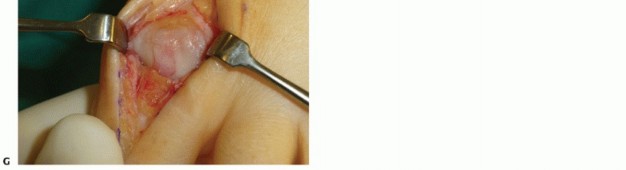

5. Extensive Plantar Release

Release of the plantar structures is very important for improving the ROM.

Because of the inhibition of dorsiflexion in the first MTP joint, contracture of the plantar structures (joint capsule, short toe flexors) has taken place.

The joint capsule and the short flexors with the sesamoid bones are released subperiosteally using a McGlamry elevator (TECH FIG 3A,B).

The phalangeal attachment of the plantar capsule and the insertion of the short flexor muscles are released (TECH FIG 3C).

This maneuver must be performed cautiously so as not to detach the tendons from their insertion.

6. TECH FIG 3 • A. Plantar release using a McGlamry elevator. B. Plantar release using a McGlamry elevator. C. Release of the distal capsule and short flexors using a scalpel. D. Plantarflexion after plantar release and resection of osteophytes.